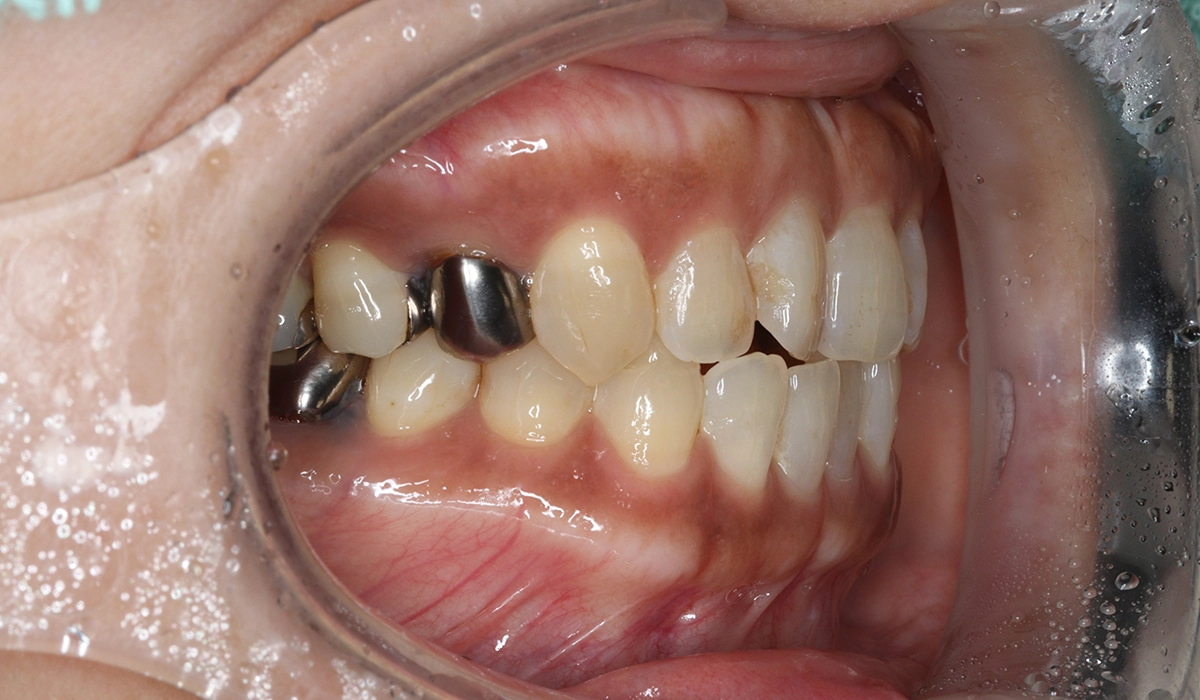

術前:右側